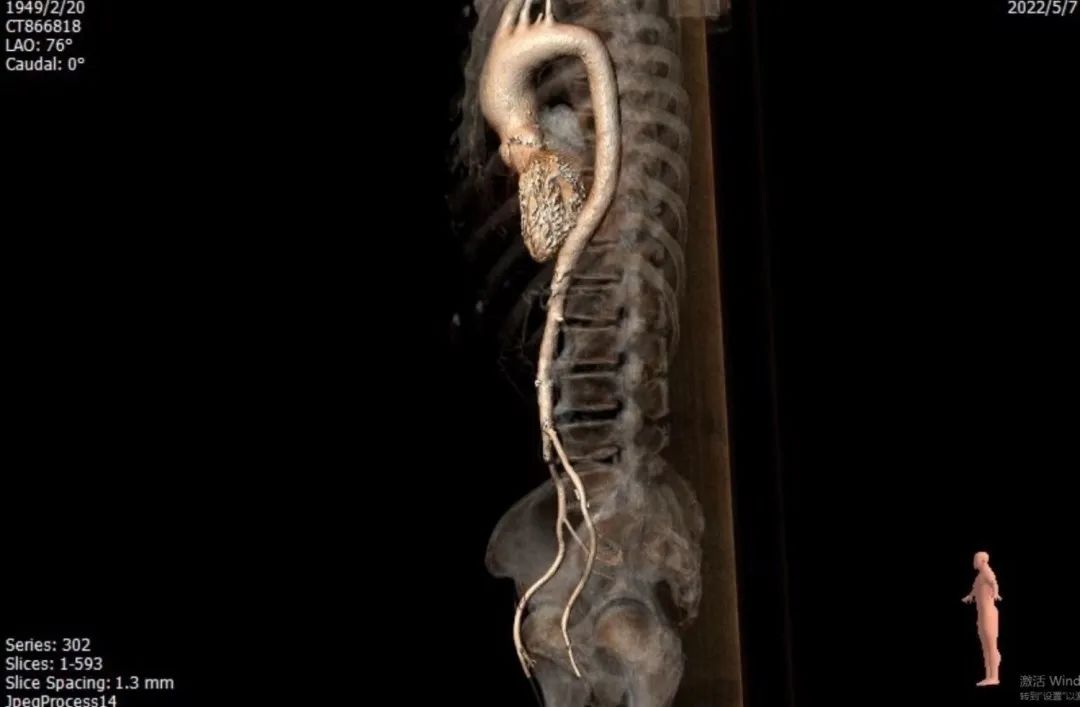

CT评估

图片

主动脉弓角度与宽度可,心脏水平夹角47°

入路血管左侧分叉高,无迂曲。左侧血管平均最小内径4.7mm,右侧血管平均最小内径4.2mm

1. 患者钙化非常严重,Type 0型二叶瓣,钙化积分高达2100+,钙化主要分布瓣叶、瓣叶交界,升主动脉严重扩张,必要时使用Snare辅助过弓和跨瓣;

2. 患者主动脉弓角度在过弓时会遇到困难,并且降主动脉明显瘤样扩张,容易产生夹层;

3. 患者入路条件不好,双侧股动脉明显狭窄,术中会采用外周预扩球囊4.0mm、5.0mm及6.0mm逐步预扩张右侧股动脉和右髂动脉,造影验证预扩后情况,根据预扩张后情况决定是否采用右侧股动脉为主入路血管;

4. 患者入路血管左侧分叉高,无迂曲。